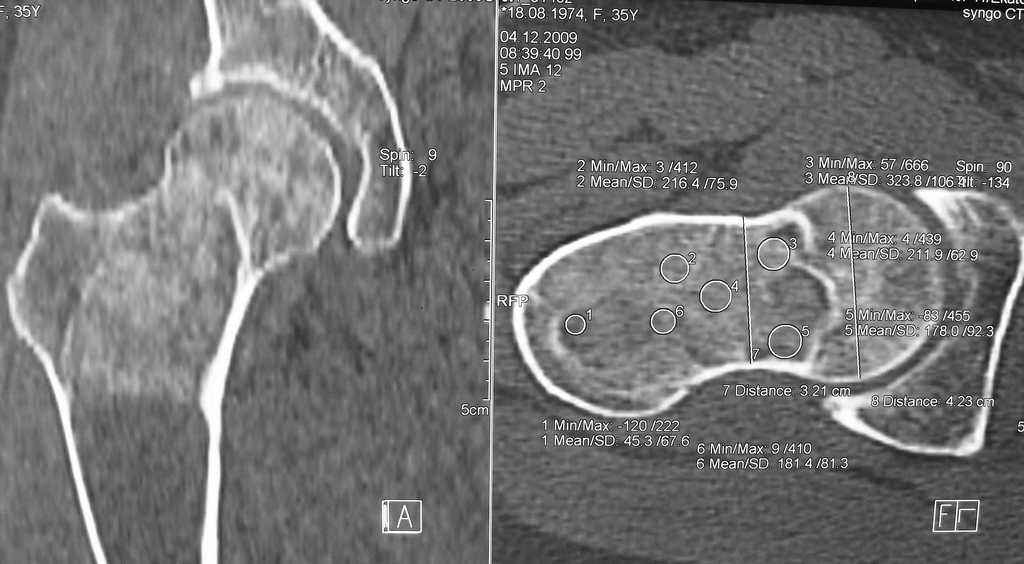

Re: Фиброзная дисплазия-продолжение

Maxim Agalakov 14 Январь 2010, 23:39

Устьянцев Ибрагимов 15 Январь 2010, 08:10

Уважаемая коллега!

Один из вариантов выбора- резекция пораженного участка, замещение дефекта по Илизарову, с последующим синостозированием или эндопротезированием.

Djoldas Kuldjanov 24 Январь 2010, 23:40

Елена,

При наличии в института сосудистых хирургов, как альтернативный метод можно было бы предложить графт как показано на снимке.

Elena Reyno 28 Январь 2010, 16:55

Большое спасибо, уважаемые коллеги! Большинством мнений склоняемся к резекции патологического очага с замещением дефекта аллокостью. Но вопрос пока остаётся открытым.

Отправитель: valeevmm 06 Февраль 2010, 10:16

Здраствуйте, коллега! Загляните, пожалуйста, на мой сайт valeevmm.ru. Там в разделе "Клинические случаи" имеется случай лечения паицента с фиброзной дисплазией бедренной кости васкуляризированным аутотрансплантатаом из фрагмента малоберцовой кости. Спасибо. С уважением, профессор Валеев (г. Уфа).

Илья Иофин 31 Январь 2010, 03:39

Я бы сделал открытый латеральный доступ к прохимальной части бедра и провёл кюретаж. Потом бы поставил штырь типа Gamma nail. Оставшуюся от кюретажа полость следует заполнить костным цементом. Проблема при фиброзной дисплазии в том, что она через год два возвращается и "съедает" аллокость, как будто операции и не делали.

Эту операцию я бы делал только если у пациента есть симптомы боли. Если их нет, то делал бы периодический рентген бедра.